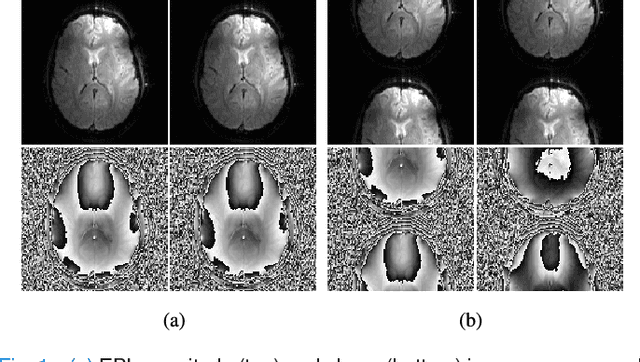

Abstract:Purpose: We propose and evaluate a new structured low-rank method for EPI ghost correction called Robust Autocalibrated LORAKS (RAC-LORAKS). The method can be used to suppress EPI ghosts arising from the differences between different readout gradient polarities and/or the differences between different shots. It does not require conventional EPI navigator signals, and is robust to imperfect autocalibration data. Methods: Autocalibrated LORAKS is a previous structured low-rank method for EPI ghost correction that uses GRAPPA-type autocalibration data to enable high-quality ghost correction. This method works well when the autocalibration data is pristine, but performance degrades substantially when the autocalibration information is imperfect. RAC-LORAKS generalizes Autocalibrated LORAKS in two ways. First, it does not completely trust the information from autocalibration data, and instead considers the autocalibration and EPI data simultaneously when estimating low-rank matrix structure. And second, it uses complementary information from the autocalibration data to improve EPI reconstruction in a multi-contrast joint reconstruction framework. RAC-LORAKS is evaluated using simulations and in vivo data, and compared to state-of-the-art methods. Results: RAC-LORAKS is demonstrated to have good ghost elimination performance compared to state-of-the-art methods in several complicated acquisition scenarios (including gradient-echo brain imaging, diffusion-encoded brain imaging, and cardiac imaging). Conclusion: RAC-LORAKS provides effective suppression of EPI ghosts and is robust to imperfect autocalibration data.

Abstract:Structured low-rank matrix models have previously been introduced to enable calibrationless MR image reconstruction from sub-Nyquist data, and such ideas have recently been extended to enable navigator-free echo-planar imaging (EPI) ghost correction. This paper presents novel theoretical analysis which shows that, because of uniform subsampling, the structured low-rank matrix optimization problems for EPI data will always have either undesirable or non-unique solutions in the absence of additional constraints. This theory leads us to recommend and investigate problem formulations for navigator-free EPI that incorporate side information from either image-domain or k-space domain parallel imaging methods. The importance of using nonconvex low-rank matrix regularization is also identified. We demonstrate using phantom and \emph{in vivo} data that the proposed methods are able to eliminate ghost artifacts for several navigator-free EPI acquisition schemes, obtaining better performance in comparison to state-of-the-art methods across a range of different scenarios. Results are shown for both single-channel acquisition and highly accelerated multi-channel acquisition.